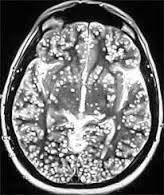

Evaluation: He had hemoglobin levels of 14.9gm/dl ,platelet count WBC count were normal . He had normal Liver and renal functions .CT scan head was done Fig1 it showed diffuse cysts in the brain suggestive of Neurocysticercosis and later the serology came positive for Neurocysticercosis.

| Fig 1 CT scan head showing cysticercosis. |